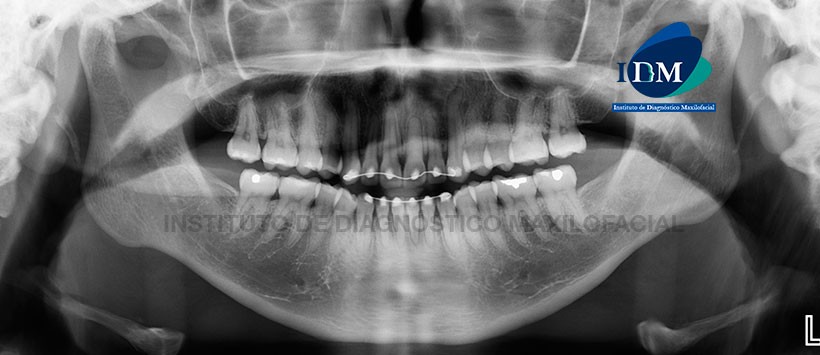

Paciente de 26 años de edad acude al Instituto de Diagnóstico Maxilofacial para evaluación imagenológica de los incisivos superiores.

A la evaluación panorámica se evidencio la ausencia de las terceras molares, alambre de contención en el sector dentario anterior, cálculos pulpares en sector dentario posterior y múltiples restauraciones coronarias. Siendo lo mas reslatante la aparente obliteración total del conducto radicular perteneciente a la pieza 21. (Figura 1)